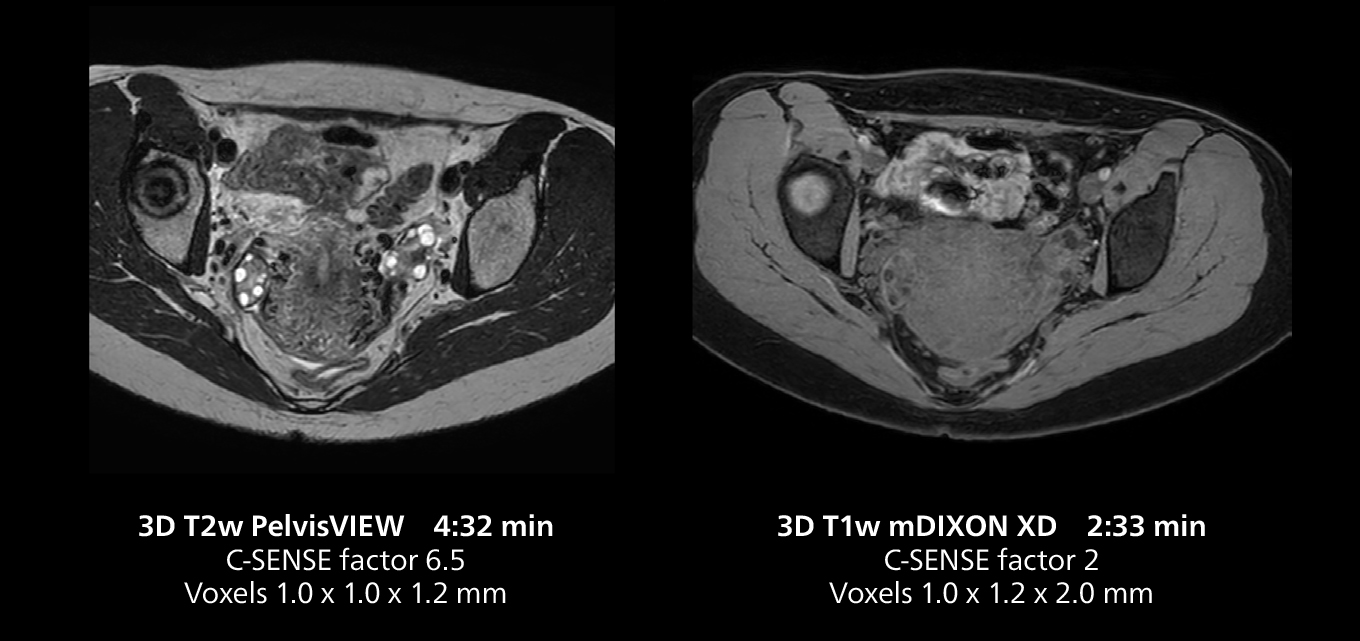

Female pelvis imaging

This MRI case illustrates good resolution and imaging quality obtained within reasonable scan times using the MR 5300 1.5T system with the anterior torso cardiac coil that allows use of a large field of view (FOV).

Imaging speed benefits diagnostic confidence

The MR 5300 with Compressed SENSE is up to 50%** faster for many exams. It can provide routine exams in less than 5 minutes and whole-body exams in less than 20 minutes. Saint-Augustin has taken advantage of that speed to create highly efficient protocols. The hospital’s standard stroke protocol is just about 8 minutes, and standard ENT, prostate PIRADS staging, and endometriosis studies all clock in at just about 10 minutes.***

“We have more speed in 3D sequences,” Dr. Gellée states. “With Compressed SENSE, we can replace two or three 2D scans withone high-quality 3D scan. High quality additional orientations are then obtained by post-processing of the 3D data set, thus saving scanning time.”